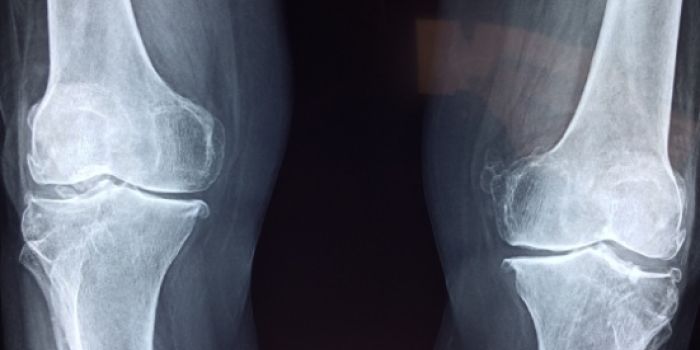

Il monitoraggio regolare della salute ossea è fondamentale per la prevenzione e la diagnosi precoce dell’osteoporosi. Attraverso esami specifici come la densitometria ossea (MOC o DEXA), è possibile valutare la densità minerale ossea e identificare eventuali riduzioni prima che si verifichino fratture.

Secondo le raccomandazioni della International Osteoporosis Foundation e della Società Italiana dell’Osteoporosi (SIOMMMS), sottoporsi periodicamente a controlli, soprattutto dopo la menopausa o in presenza di fattori di rischio come familiarità, sottopeso o uso prolungato di corticosteroidi, permette di adottare tempestivamente le necessarie misure correttive.